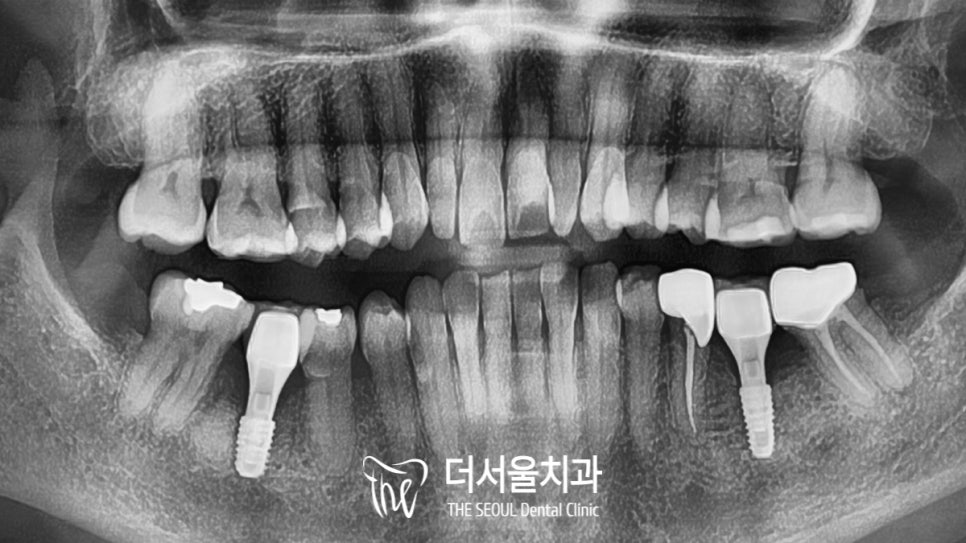

파노라마로 볼 수 있듯이

염증으로 인한 골소실이 나타나 있었는데요.

20년이 지나 골소실이 심한 상태였지만

컴퓨터 분석을 통해

식립 방향과 위치를 결정했습니다.

계산된 위치 그대로

정확하고 안전한 식립을 통해

디지털 임플란트 과정을 마무리했습니다.

이곳도 좌측과 마찬가지로

디지털 임플란트 식립을 통해

개선을 하기로 했습니다.

브릿지 교체 때와 마찬가지로

분석을 통해 식립로를 파악한 뒤,

정해진 위치에 심어드리며 마무리를 했습니다.